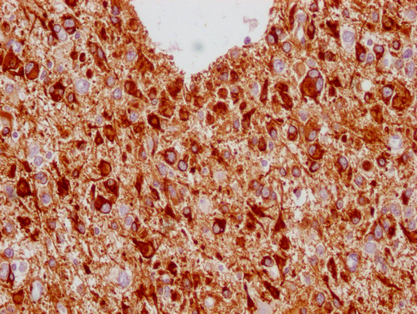

• IHC image of CSB-MA293354 diluted at 1:100 and staining in paraffin-embedded human glioma cancer performed on a Leica BondTM system. After dewaxing and hydration, antigen retrieval was mediated by high pressure in a citrate buffer (pH 6.0). Section was blocked with 10% normal goat serum 30min at RT. Then primary antibody (1% BSA) was incubated at 4°C overnight. The primary is detected by a Goat anti-mouse IgG polymer labeled by HRP and visualized using 0.05% DAB.

IHC 1:20-1:200